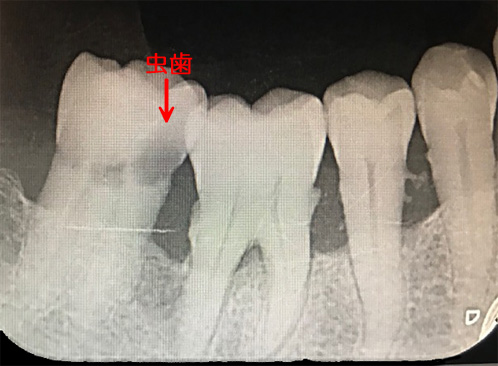

こちらはレントゲンですが、左端の奥歯に虫歯で大きな穴が開いているのがわかります。

これは77歳の女性でしたが、主訴は「歯の間にものがはさまる」でした。

こんな大きな虫歯があっても痛みはありませんでしたし、歯の上からは穴は見えませんでした。でも虫歯は

C3で歯髄(神経)まで進んでおり、抜髄(神経を取る)となりました。

このように痛みは個人差が大きいもので、痛くなってから行くのでは本当に手遅れなのです。